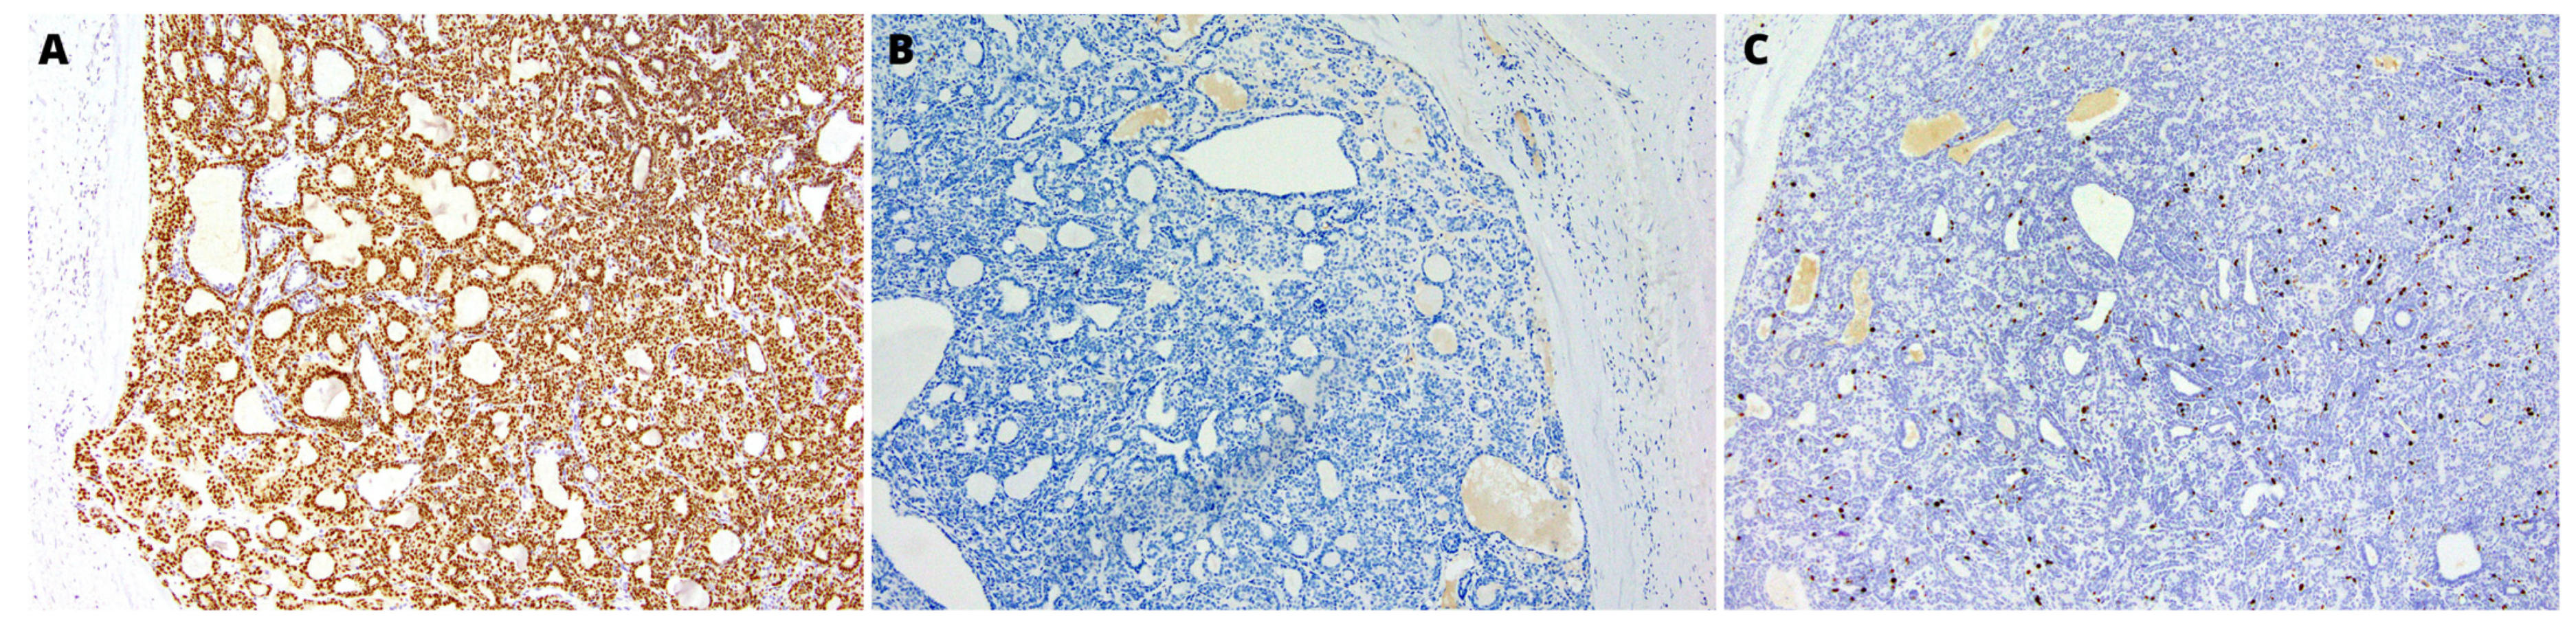

2.2. Pathology